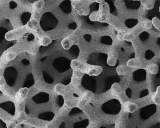

Células madre: pilar básico del proceso de renovación celular

Se multiplican mediante divisiones mitóticas para dar lugar a otras células madre idénticas. También tienen la capacidad de diferenciarse en diversos tipos de células especializadas. En tecnología cosmética hace referencia principalmente a activos de origen vegetal capaces de activar el metabolismo celular.